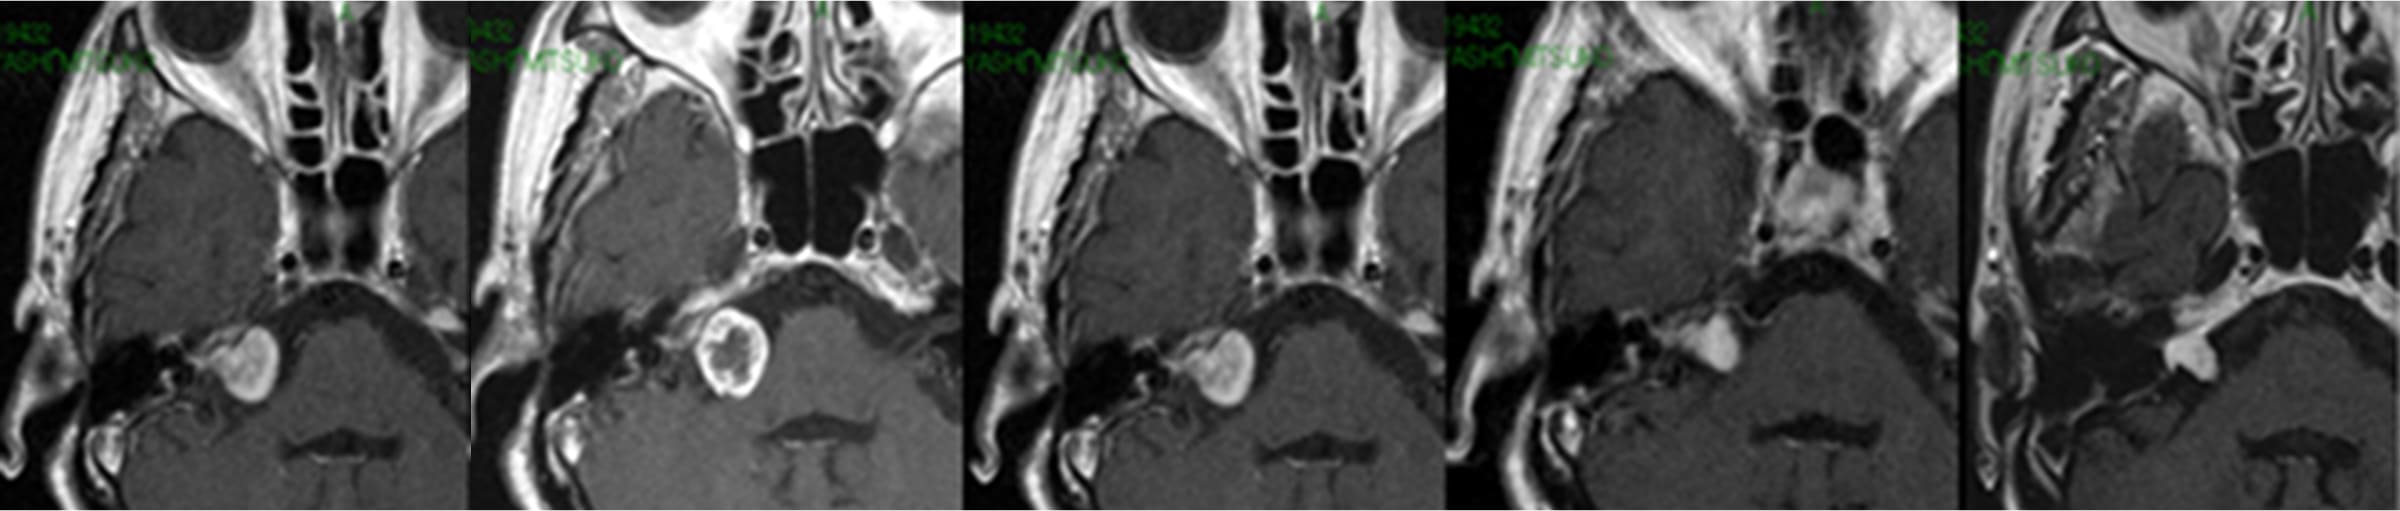

聴神経腫瘍症例ガンマナイフ後経過

半年後(左より2つ目)に炎症で一過性膨大あり、

その後1年(左より3つ目)で元に戻り、

以後縮小傾向